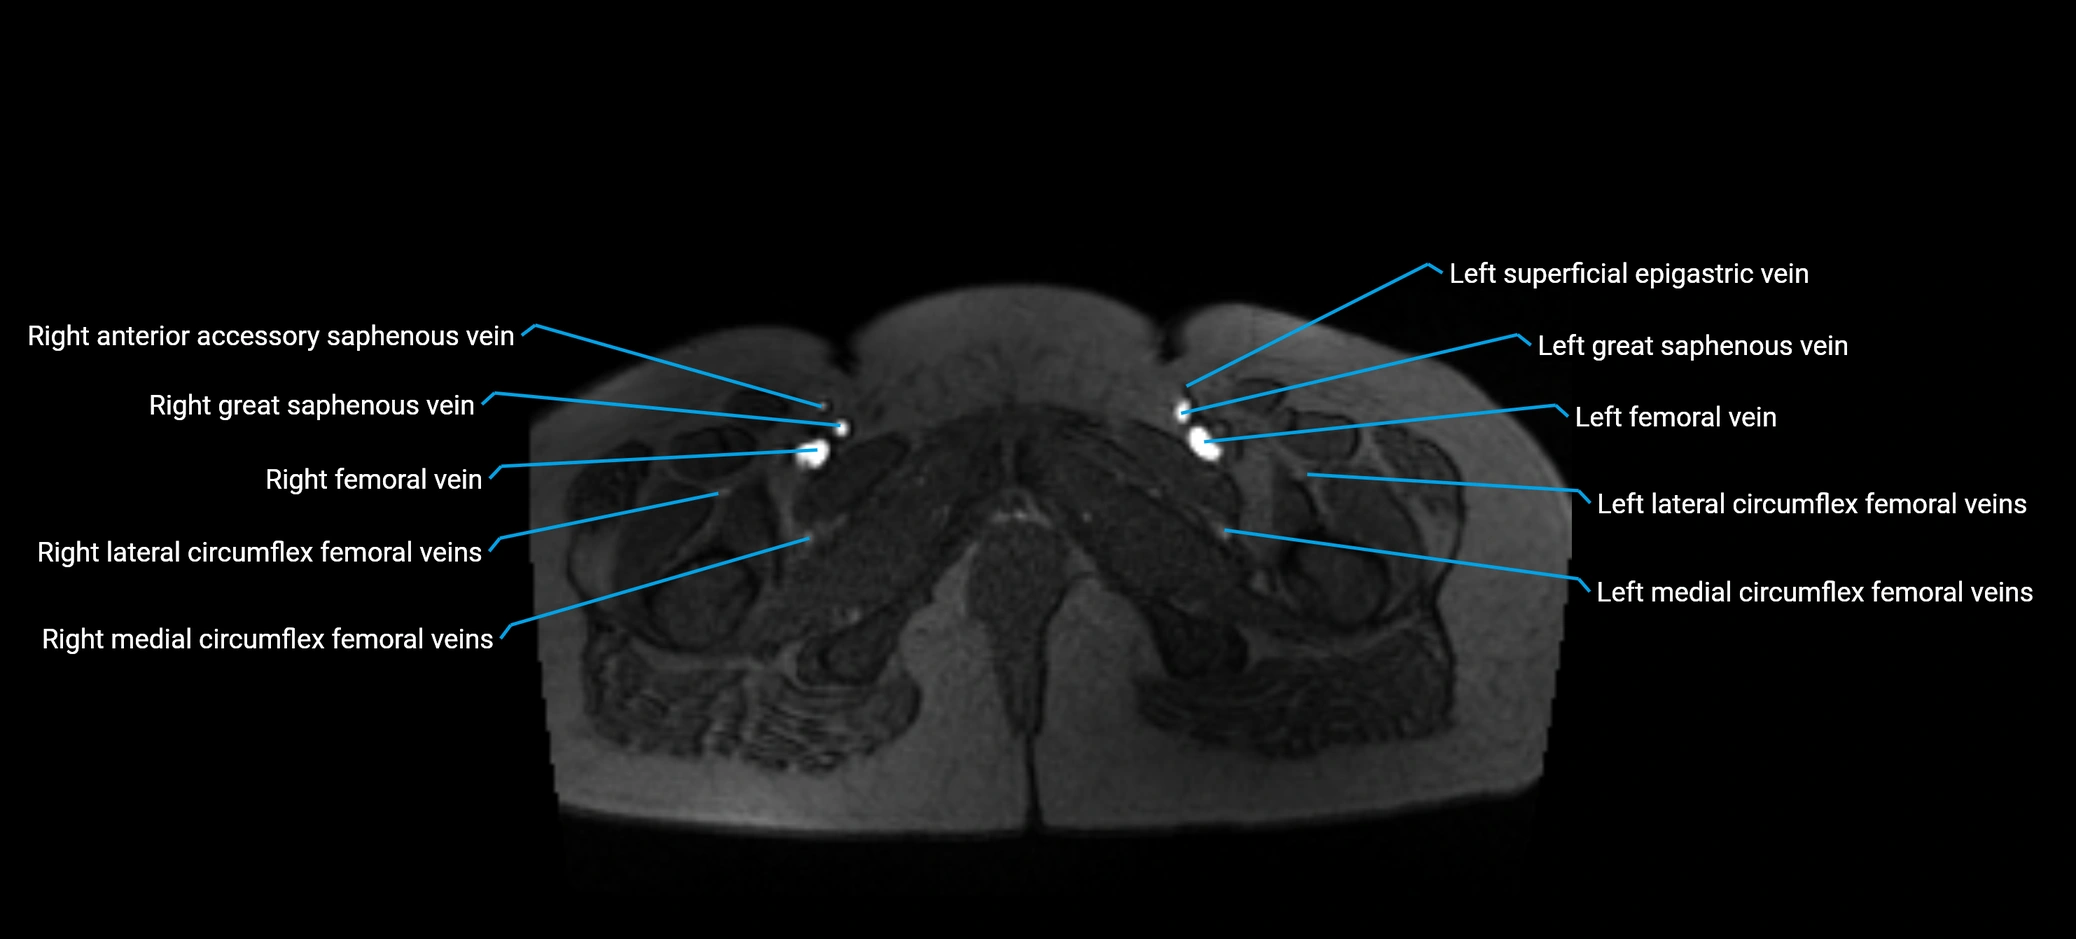

MRI image

image